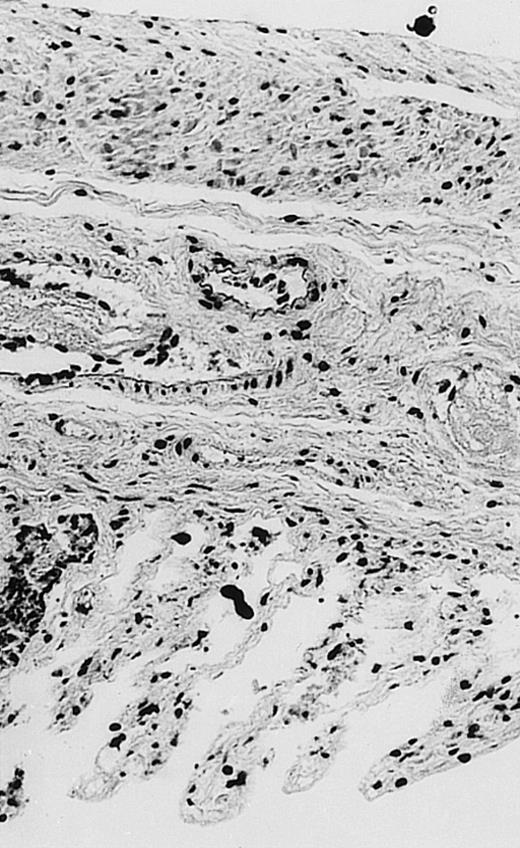

Pathologic findings in the small and large intestine were strikingly different depending on the treatment group. Figure 2A shows a representative pathologic sample from an animal assigned to the control group. Marked thinning of the bowel wall and extensive areas of epithelial cell sloughing was noted. Animals randomized to rhG-CSF treatment had minimal improvement in histologic findings with focal regions of preserved epithelium (Fig2B). Animals randomized to the rhIL-11 group showed substantial improvement with thickening of the epithelial layer and preservation of mucosal cell integrity (Fig 2C). Animals receiving both rhG-CSF and rhIL-11 had the most favorable histologic findings with normal mucosal thickness, minimal inflammatory changes, and preserved tissue architecture (Fig 2D). The composite analysis of the gastrointestinal pathology is provided in Table 1.

Histopathology of small intestinal mucosa cut in transection from an animal in each treatment group (study day 8). The upper panel (row 1) is a low power view (original magnification × 57); the lower panel (row 2) is a high power view (original magnification × 144). Note the diffuse thinning and necrosis of the mucosa with sloughing of intestinal epithelial cells in the control animal (A). There is progressive recovery of the thickness of the mucosa, reduction in inflammatory changes, and improved epithelial architecture with rhG-CSF (B), rhIL-11 (C), and combination therapy with rhG-CSF+IL-11 (D).

The beneficial effects of rhIL-11 in the neutropenic rat model may be mediated by its activity as a hematopoietic growth factor, an antiinflammatory cytokine, or its ability to maintain gastrointestinal epithelial integrity.25,33 The results of the current study would favor rhIL-11 protective effects on the intestinal epithelium as the principal mechanism protection in these animals. Maintenance of the gastrointestinal barrier function should diminish the frequency of gut translocation-derived bacterial infection after chemotherapy-induced myelosuppression and epithelial injury.25 The remarkable preservation of membrane integrity found on the gastrointestinal pathologic samples, the reduced circulating levels of endotoxin, and the reduced bacterial load in organ cultures support a dominant role for epithelial protective effects by rhIL-11 treatment in this animal model.